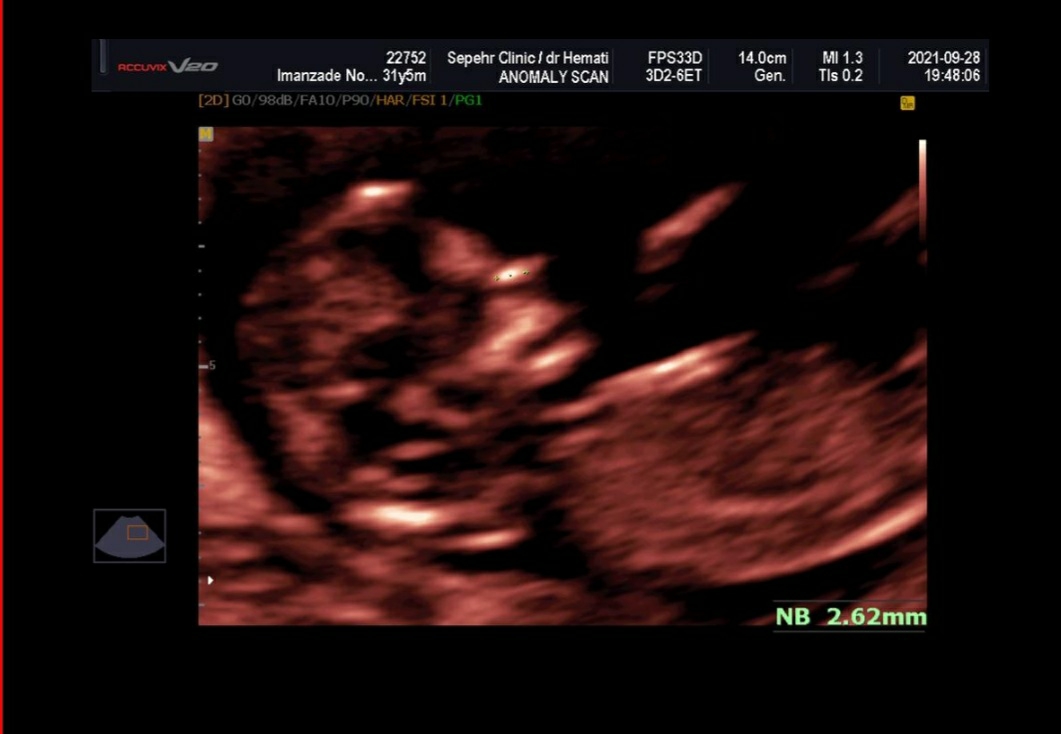

سلام به روی گلتون مامان جان

خیلی خیلی مبارکتان باشد ریسک محاسبه شده برای سندروم های ژنتیکی تریزومی ۲۱ و تریزومی ۱۸ و 13 همگی در محدوده کم خطر قرار داشته و منفی هستند. در حال حاضر نیاز به هیچ بررسی دیگری نیست جان دلم و صرفاً در هفته هجده بارداری مانند تمامی مادرانی که در محدوده کم خطر قرار دارند، سونوگرافی آنومالی اسکن برای ارزیابی ساختارهای بدن جنین و همچنین آزمایش Ntd screen برای ارزیابی اختلالات لوله عصبی (این بررسی ضرورت جدی انجام ندارد و در صورت صلاحدید پزشکتان درخواست گردد) را انجام دهید،، سونوگرافی هم خوب است❤️